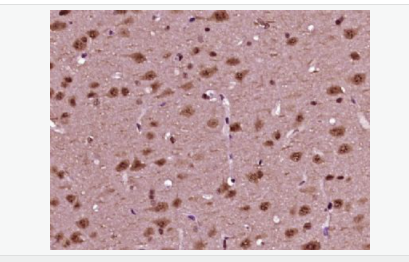

交叉反應:Human,Mouse,Rat(predicted:Pig,Cow,Sheep) 推薦應用:WB,IHC-P,IHC-F,ICC,IF,ELISA

| 產品應用 | WB=1:500-2000 ELISA=1:5000-10000 IHC-P=1:100-500 IHC-F=1:100-500 ICC=1:100-500 IF=1:100-500 (石蠟切片需做抗原修復) not yet tested in other applications. optimal dilutions/concentrations should be determined by the end user. |